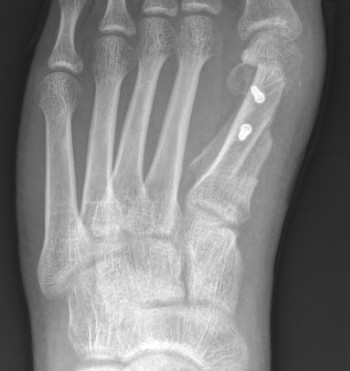

Lapidus Procedure / TMT arthrodesis + DTSP

Indications

- moderate to severe HV

- TMTJ hypermobility

- metatarsus primus varus

Technique

Triplanar correction - coronal / sagittal / rotational